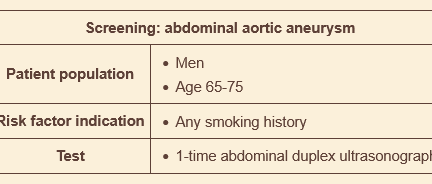

what’s the screening protocol for AAA?